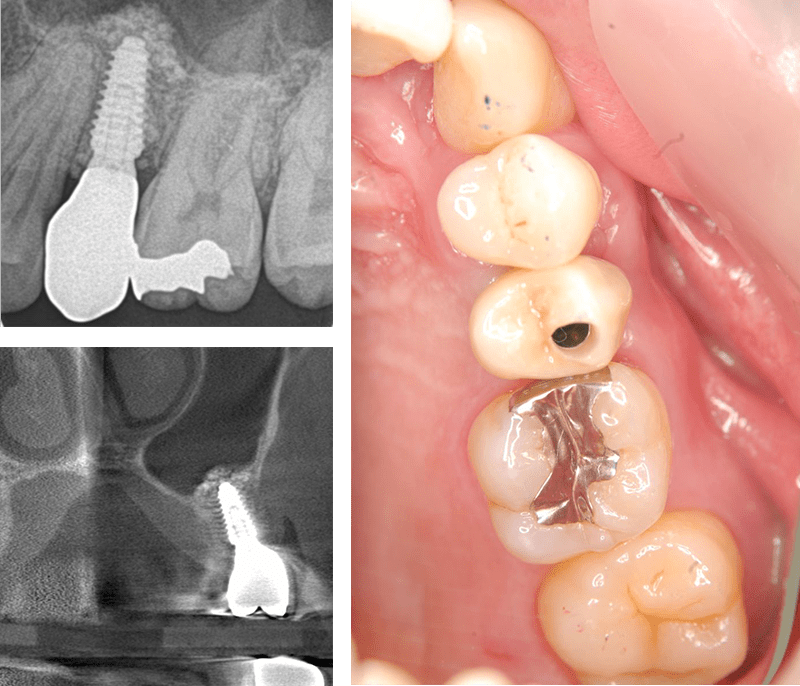

症例4【50代女性】左上6 副鼻腔膜を挙上しインプラント埋入 左上5 歯根破折の為インプラント埋入

治療前

左上5の歯根破折

治療後(10年経過)

※説明

主訴 左上奥歯で物が噛めない。入れ歯は煩わしいので、インプラントを希望。

左上第一大臼歯欠損部位は、骨の高さが3~4㎜しかなく、造骨の為にソケットリフト(骨造成)を行い、骨の高さを確保しインプラントを埋入。

約半年の免荷期間を経て、仮歯を装着、リハビリをし、約7ヶ月後にメタルボンド(金属焼付ポーセレン)を装着。

その後、左上第二小臼歯の歯根破折の為に、2本目のインプラントを埋入。(抜歯即時埋入)

リスクとしては、外科的侵襲がある。デメリットは、保険外診療の為、経済的負担がある。

費用 111万(オペ。ソケットリフト・人工骨・採血による濃縮血小板生成・仮歯・最終補綴物まで含む)